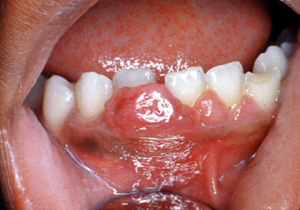

Cuando estas lesiones periféricas están casi exclusivamente compuestas de fibroblastos y células  endoteliales y  muchas células gigantes, la lesión es denominada Granulom de Células Gigantes. Clínicamente, pueden parecerse al granuloma periférico o  pueden ser bastante vascular y parecerse el granuloma piógeno.

Este ejemplo es bastante vascular. Ha cambiado de sitio al incisivo central hacia lingual. Los granulomas de  celulas gigantes tienen un mayor potencial de crecimiento  que el granulomas periférico y puede cambiar de lugar  los dientes.

Aquí hay un ejemplo típico de un granuloma de celulas gigantes; sin embargo, sólo por la biopsia  escisional  es posible el diagnóstico.